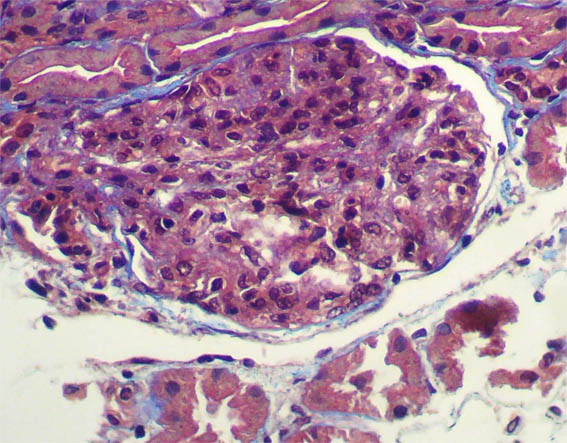

Figura 4.

Tricrómico de Masson, X400.